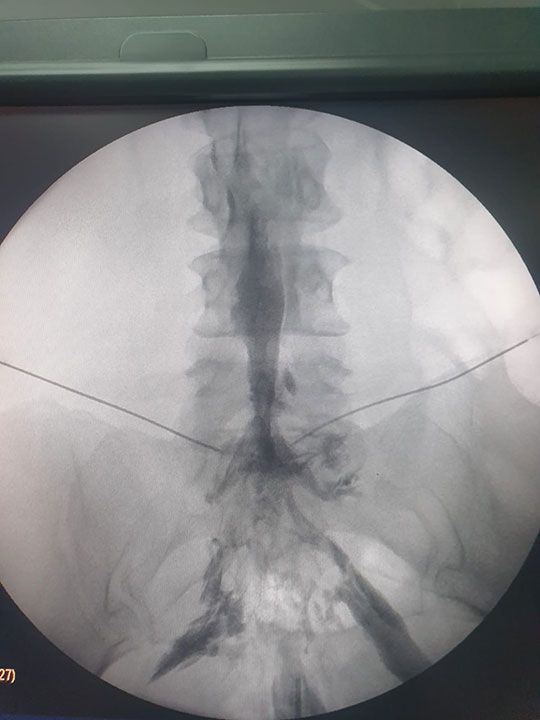

Lumbalgia

Puede ser una fuente de malestar persistente y limitaciones en la actividad física, tenemos tratamientos personalizados que se centran en aliviar el dolor lumbar y mejorar la funcionalidad de la columna vertebral ya que nuestro objetivo es proporcionar alivio efectivo y duradero a los pacientes que sufren de esta condición común.